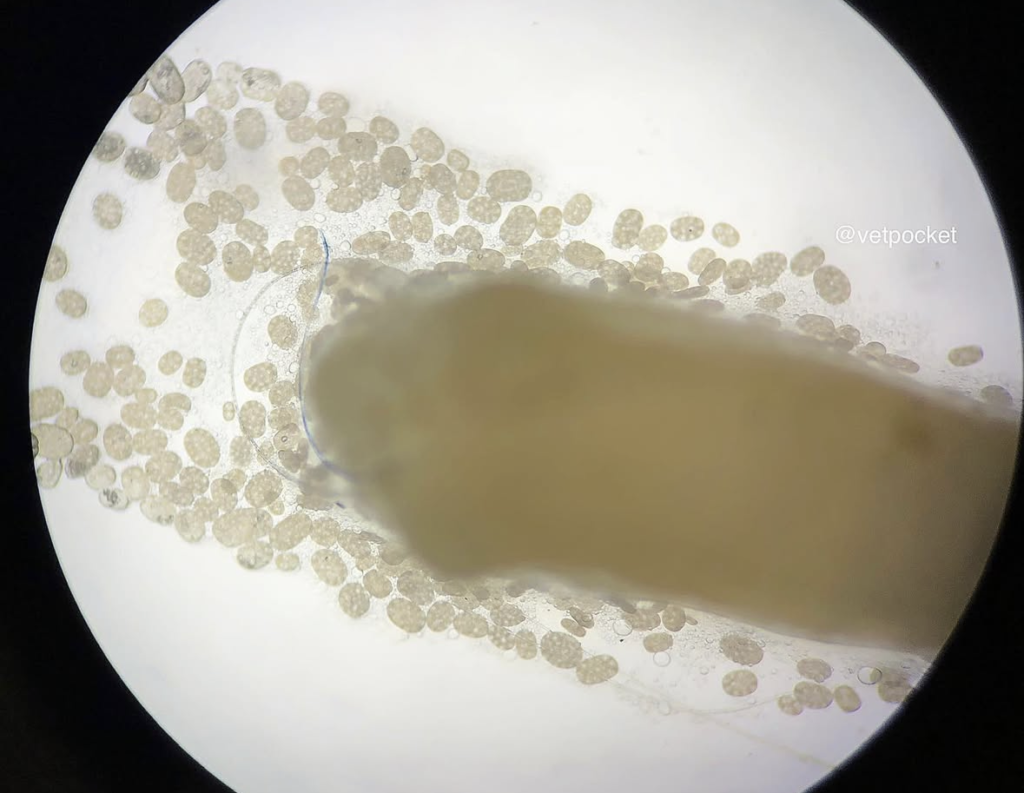

(iii) Microscopic exam of an intact proglottid placed on a slide, and seeing if the proglottid is releasing its egg packets (like a chicken laying eggs).

(iv) Microscopic exam of a proglottid (with or without a few drops of water or saline) crushed between a slide and a cover slip to see if egg packets are appreciated.

Adult tapeworms are ~15 to 70 cm in length, and consist of a head segment (scolex), a neck segment, and a body (strobila) made up of multiple segments (proglottids). Each proglottid is oblong and roughly the size of a grain of rice, ~10 to 12 mm in length, and contain bilateral genital pores. Each egg packet is round to ovoid, ~120 to 200 mcm in length, and contains ~2 to 63 (average is ~25 to 30) individual eggs. Individual eggs are round to oval, pale yellow, ~35 to 60 mcm in diameter, and contain an oncosphere that has 6 hooklets (hexacanth embryo).